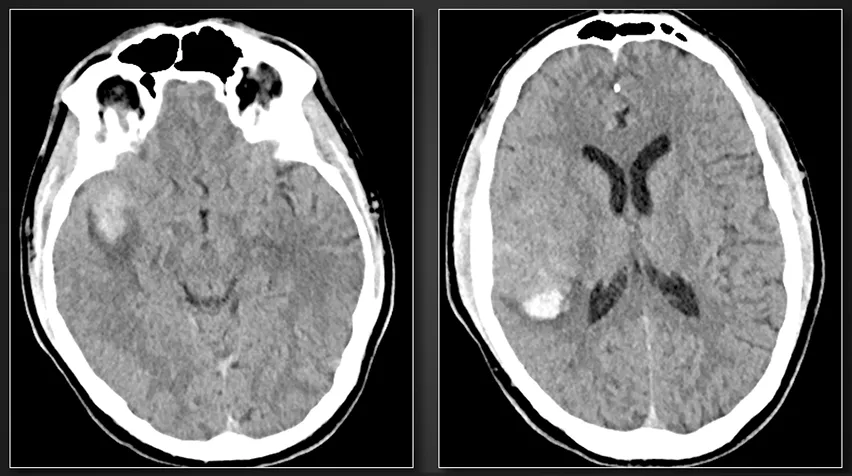

一名33岁男性患者,既往身体健康,因出现发热、寒战及外周脓毒性栓子而就诊,检查发现存在感染性心脏瓣膜赘生物。患者主要临床表现为头痛与左上肢无力;头颅影像学检查揭示一处形态不规则、呈分叶状的7×8×9mm大脑中动脉真菌性动脉瘤,该动脉瘤累及多个M3分支,并伴有蛛网膜下腔出血。同时,影像学还可见由脓毒性栓子导致的多灶性、小灶性脑实质内出血。医疗团队建议行动脉瘤夹闭截瘤联合血运重建术。

术前影像